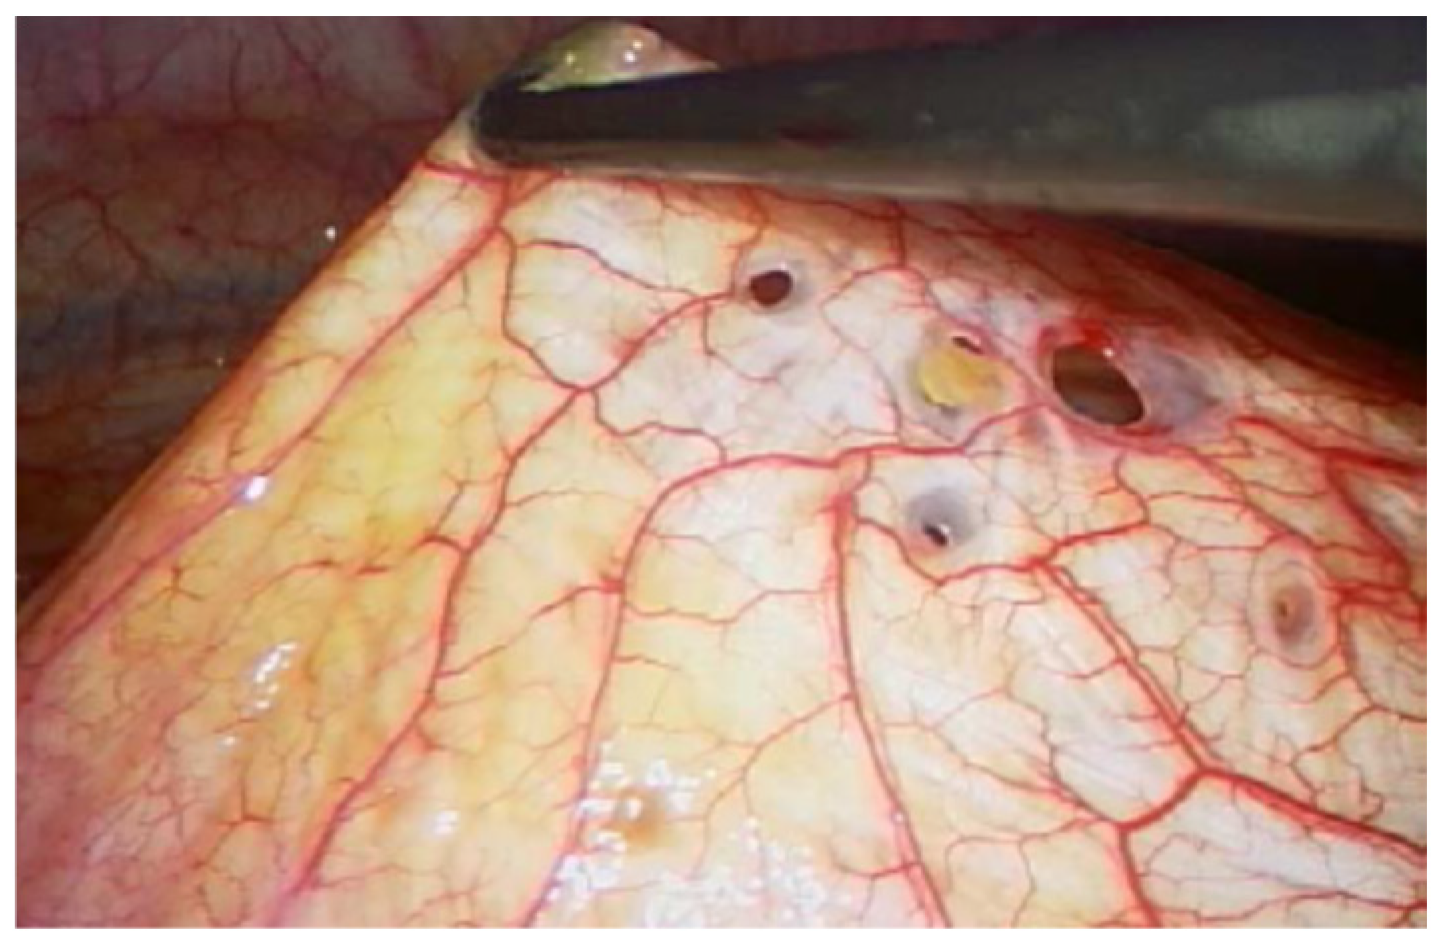

2.4. Diagnostic Assessment and Therapeutic Intervention